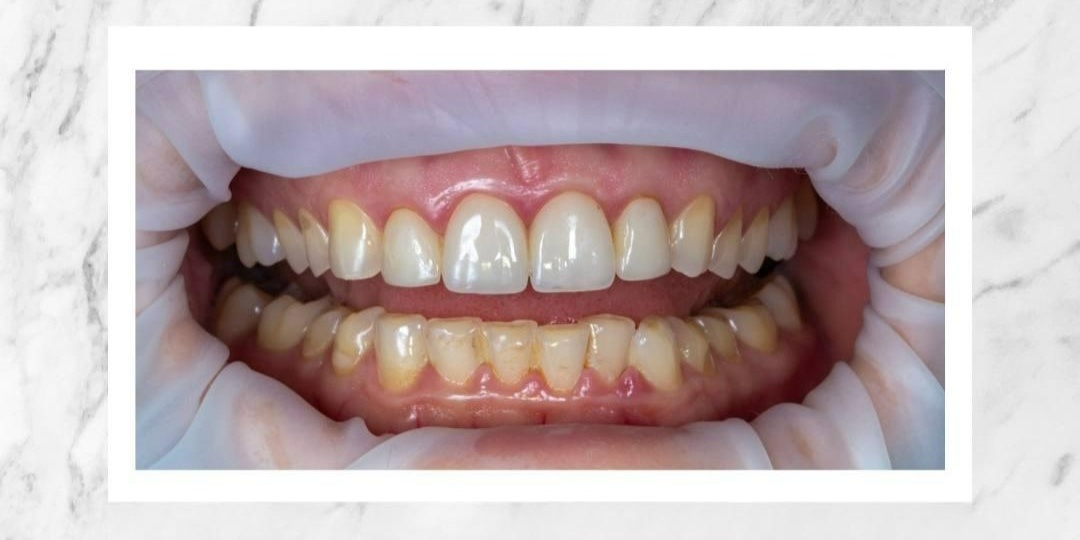

Этим винирам 20 лет!

К нам обратилась пациентка, которая ранее проходила ортопедическое лечение у главврача нашей клиники Узунян Наринэ Адольфовны, когда она еще только закончила ординатуру на кафедре университета. Очень интересно наблюдать за динамикой пациентов спустя десятилетия. А здесь прошло целых 20 лет! Все зубы пациентки за это время разрушились и подверглись износу, а виниры стоят, как в первый день. Но с чем же пришла пациентка на этот раз? Давайте рассмотрим подробнее этот клинический случай и поймем, какой вызов мы приняли. Когда пациентка обратилась к Наринэ Адольфовне в первый раз, она морально не была готова к большой ортопедии, был лишь запрос на эстетику улыбки. Перед врачом стояла задача: защитить только центральные зубы от стирания и решить эстетический вопрос. Все эти годы после установки виниров пациентка ходила с красивыми внешне зубами, но только сейчас созрела для того, чтобы более серьезно заниматься своей зубочелюстной системой. Что мы увидели, когда пациентка пришла к нам в клин

На фото — моя пациентка до начала исправления прикуса.

Нижняя треть буквально «срезала» её женственность, придавая маскулинность. Но посмотрите, что происходит в процессе: